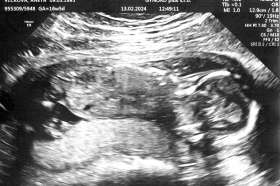

Tomášek - ještě v bříšku

2023-09-26